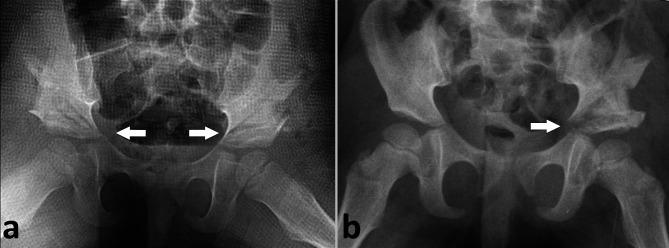

We retrospectively reviewed the records of 95 hips with developmental dysplasia of the hip who were treated with Dega pelvic osteotomy. Hips were divided into 2 groups according to medial wall disruption: group A included the hips with medial wall disruption, while group B included the hips without disruption. Preoperative, immediate postoperative, 12 weeks and last follow-up anteroposterior radiographs of the pelvis were reviewed for changes in the acetabular index (AI) between groups.

There were 22 hips in group A and 73 hips in the group B. Preoperative (34.6 versus [vs] 37.2, =0.231), postoperative (17.9 vs 18.4, =0.682), 12th week (18 vs 18, =0.504) and last follow-up (13.3 vs 15.1, =0.097). The acetabular index measurements were comparable between the groups. Corrections achieved during surgery, and during the follow-up period were also comparable between the two groups, indicating no loss of radiographic correction caused by medial wall disruption. Ninety one percent of the patients in group A and 90% of group B achieved good or excellent results according to the Severin classification (=0.944).

Our study shows that disruption of the medial wall did not have a significant detrimental effect on radiographic correction when performing Dega osteotomy.